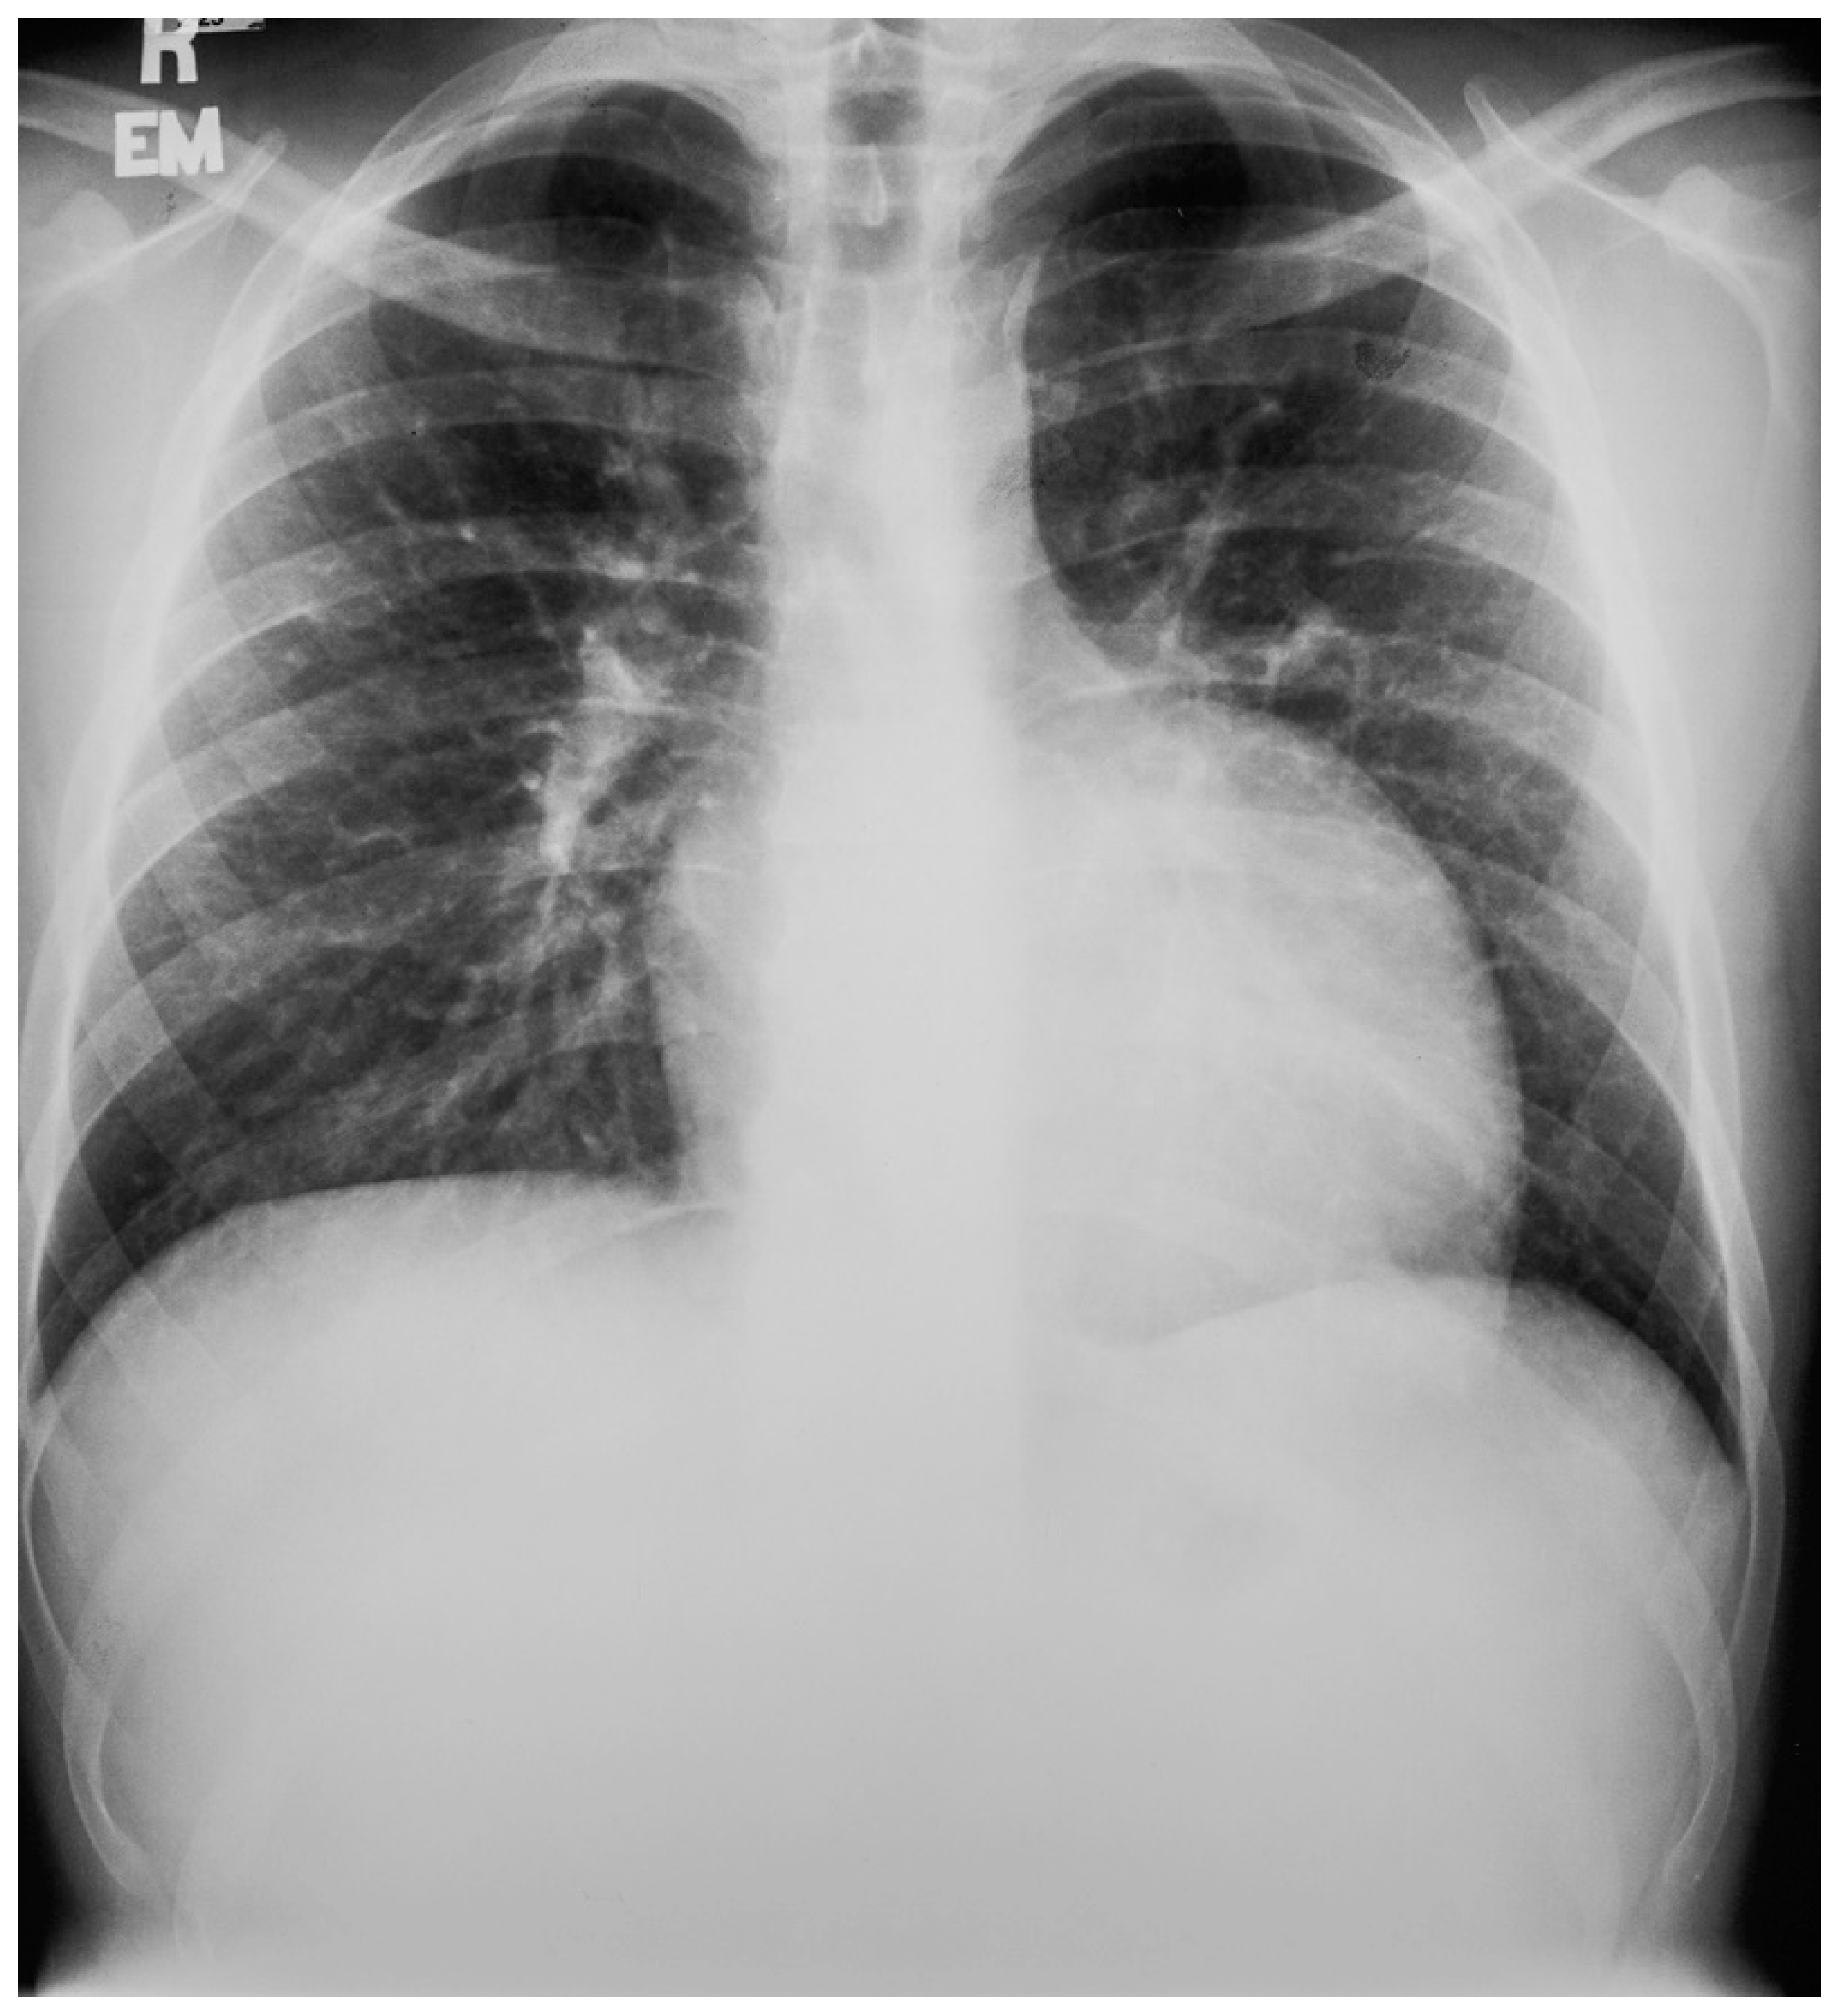

Figure 23.

Posteroanterior chest X-ray in an adult with previously operated tetralogy of Fallot: the chest X-ray was obtained in a 21-year-old female with exertional dyspnea. She was cyanotic at birth and diagnosed with tetralogy of Fallot. She had a Blalock-Thomas-Taussig (BTT) shunt (palliative subclavian artery to pulmonary artery shunt) at 10-months-of-age. At 3-years-old she underwent complete repair with closure of the ventricular septal defect, right ventricular (RV) outflow tract reconstruction with pericardium, with transannular patch and ligation of the BTT shunt. This posteroanterior chest X-ray is well centered and the inspiration is good. The cardiothoracic ratio is increased and the cardiac silhouette is boot-shaped (“coeur en sabot”). The right heart border is prominent, suggesting right atrial enlargement. The pulmonary vascularity is normal and the lung fields and pleura are clear.